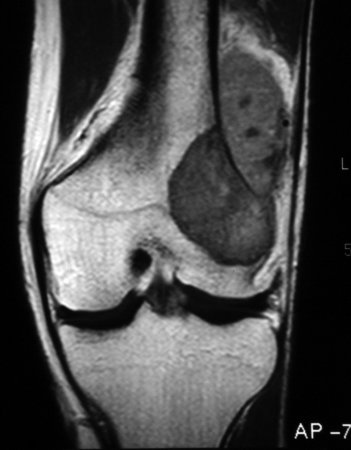

An MRI with gadolinium contrast is the test of choice to evaluate tumour extension within the bone and soft tissue. It also identifies skip metastases.[23][Figure caption and citation for the preceding image starts]: Magnetic resonance imaging, coronal view; osteosarcoma of distal femur showing low-intensity signal; T1-weighted image; actual intra-osseous and extra-osseous tumour extent is also appreciatedPersonal collections of Dr Michael J. Klein and Dr Luminita Rezeanu [Citation ends].

Result

low signal on T1-weighted images; high signal on T2-weighted images; fluid levels